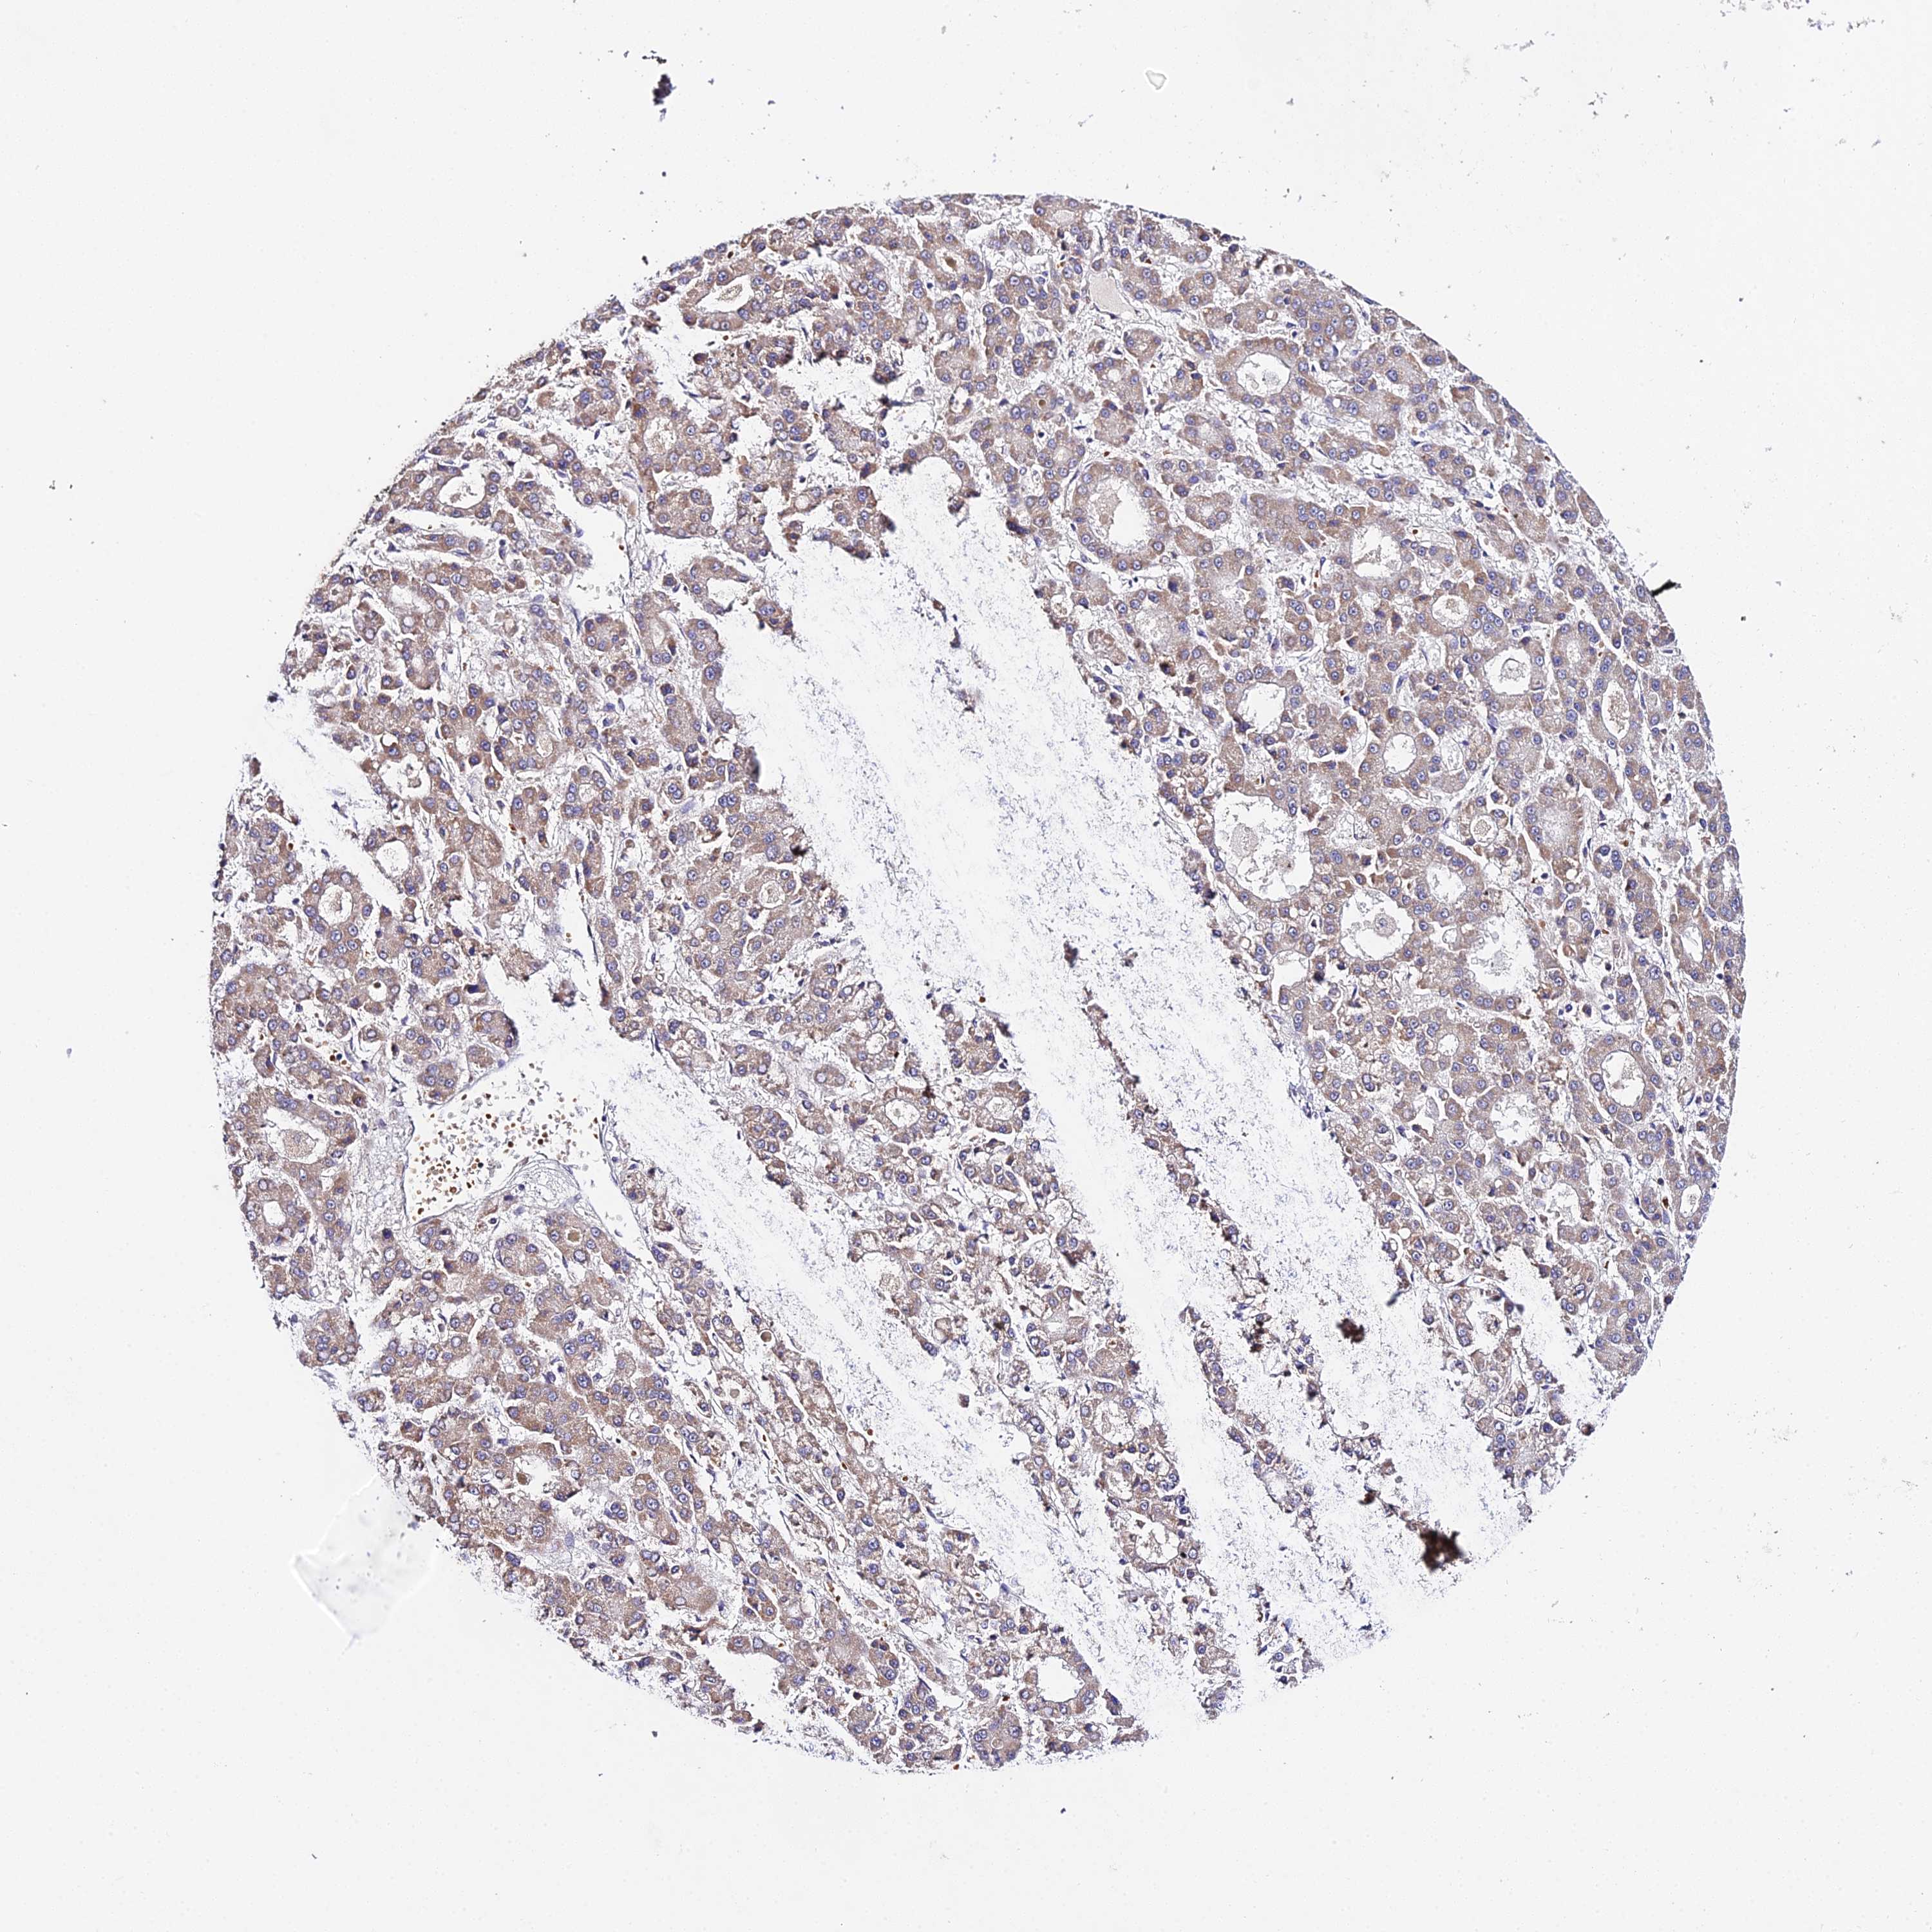

LIVER CANCER - Protein expressioni

A mouse-over function shows sample information and annotation data. Click on an image to view it in a full screen mode. Samples can be filtered based on level of antibody staining by selecting one or several of the following categories: high, medium, low and not detected. The assay and annotation is described here.

Note that samples used for immunohistochemistry by the Human Protein Atlas do not correspond to samples in the TCGA dataset.

Antibody stainingi

Antibody staining in the annotated cell types in the current human tissue is reported as not detected, low, medium, or high, based on conventional immunohistochemistry profiling in selected tissues. This score is based on the combination of the staining intensity and fraction of stained cells.

Each image is clickable and will lead to virtual microscopy that enables deeper exploration of all samples and also displays staining intensity scores, fraction scores and subcellular localization as well as patient and tissue information for each sample.

Antibody HPA042994

Staining

High

Medium

Low

Not detected

Intensity

Strong

Moderate

Weak

Negative

Quantity

>75%

75%-25%

<25%

None

Location

Nuclear

Cytoplasmic/membranous

Cytoplasmic/membranous,nuclear

Cholangiocarcinoma

Carcinoma, Hepatocellular, NOS